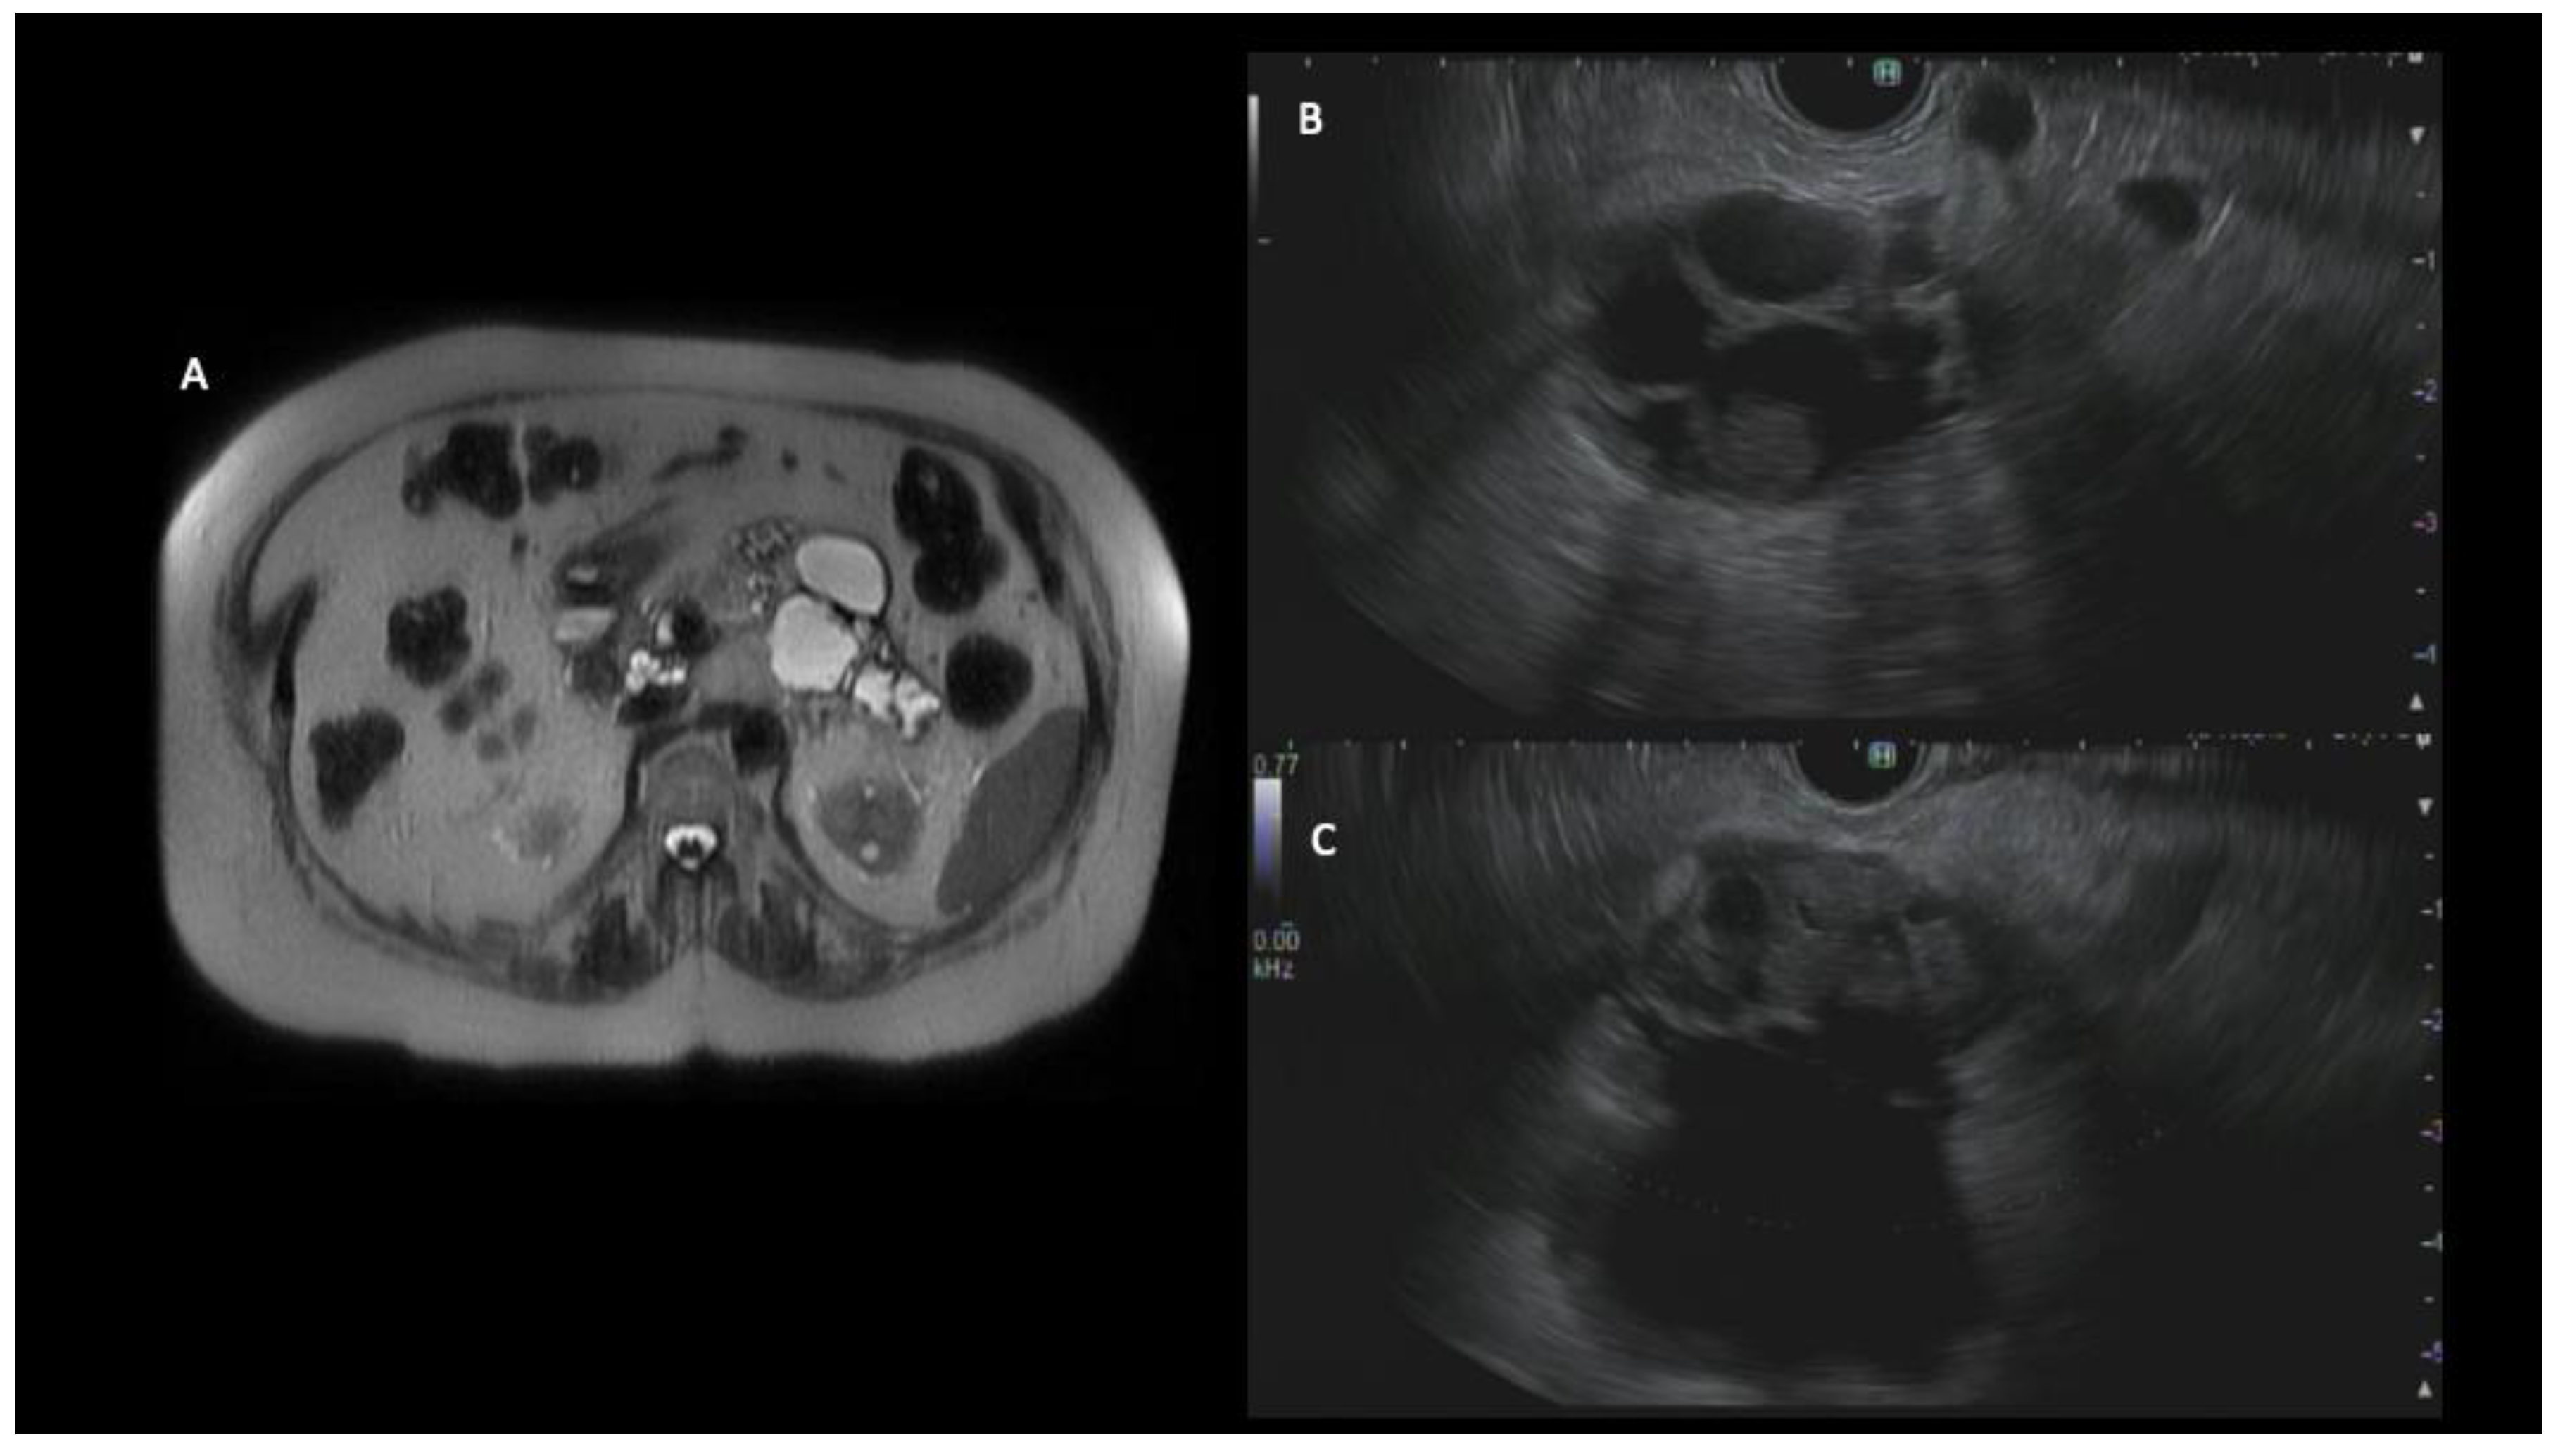

Figure 2. MRI of a 79-year-old female showed numerous cystic lesions with rapidly enlarging cysts in the distal body and tail of the pancreas (A). An endoscopic ultrasound demonstrated an approximately 50 mm cyst in the body of the pancreas associated with mural nodularity and pancreatic ductal dilation up to 20 mm (B,C). A fine-needle biopsy was obtained and showed evidence of at least high-grade dysplasia. The patient underwent distal pancreatectomy and was diagnosed with invasive moderately differentiated adenocarcinoma (T3N0M0).